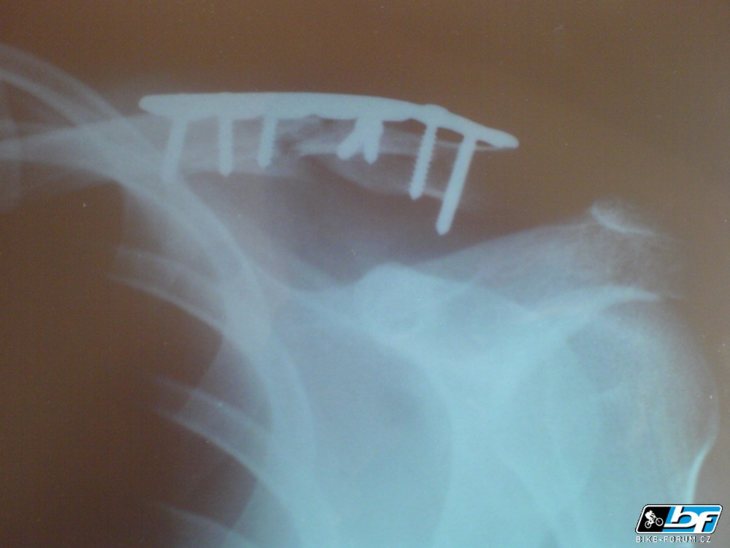

moje rameno

střet mé klíční kosti s kořenem

(vloženo 31.8.07)